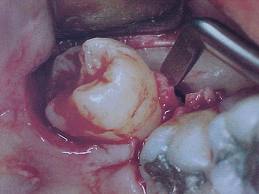

La no extracción a tiempo de las muelas del juicio puede acarrear diversos problemas. El Dr. René Latorre Cirujano-Dentista de Santiago de Chile, señala que “dependiendo de la situación original del molar del juicio; puede generarse una pericoronaritis (dolorosa inflamación de la encía de ese sector), o una caries por decúbito (contra el molar anterior), y si el molar no está erupcionado, podría generarse un quiste.”, entre otras.

“Las complicaciones post-operatorias indudablemente dependerán del estado de salud previa del paciente, de qué tan trabajoso fue el procedimiento quirúrgico y de cómo se manejó farmacológicamente el pre y el post-operatorio”, afirma el profofesor Dr. Ricardo Moreno Silva, Jefe de Cátedra de Patología Oral de Facultad de Odontología de la Universidad de Valparaíso.

Entre las posibles complicaciones, el Dr. Moreno indica que puede presentarse: ”sangramiento, que se evitará con estudios previos; infección, que se prevendrá y de aparecer deberá ser tratada con antibióticos; hinchazón, la cual requerirá del uso de compresas de hielo sobre la zona intervenida y dosis de antiinflamatorios; y dolor, que estos últimos medicamentos también disminuirán o, de ser necesario, se prescribirán analgésicos”.